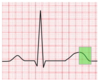

The airway pressure in this waveform clearly depicts dynamic hyperinflation, otherwise known as breath stacking. Patients with COPD have a longer expiratory time constant, and this means they require a longer period of time to exhale fully.

Of the answer choices provided, there are two options that reverse dynamic hyperinflation. By reducing the respiratory rate, the patient will spend more time over the course of a minute in E time. If PEEP becomes dangerously elevated, the definitive treatment for dynamic hyperinflation is to remove the patient from the ventilator.

Increasing inspiratory time is another way of saying reducing expiratory time, so this choice will actually make the patient’s condition worse. The inspiratory flow determines how fast the tidal volume is delivered to the patient. Increasing the inspiratory flow will deliver the preset tidal volume faster, and this does nothing to facilitate expiration.